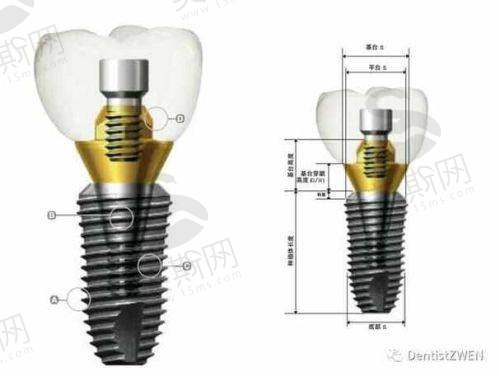

1. 牙齿种植中 心:开展即刻种植、即刻负重、全口/半口种植修复、骨增量技术(GBR/Onlay植骨)、上颌窦内外提升等,尤其擅长高龄患者复杂条件种植,采用“数字化导板 + 微创种植”技术,实现术后24小时正常进食。

哈尔滨优诺博士口腔(优诺集团)的核心特色技术为“数字化精细种植技术体系”,该技术融合3D导航种植、即刻负重、全程微创三大核心优势,实现种植手术精细度达0.1mm级误差。具体技术亮点包括:

3D导航种植技术:通过德国西门子大视野CBCT获取患者牙槽骨三维数据,结合CAD/CAM系统设计种植方案,3D打印个性化导板精细定位种植体角度、深度与位置,避免损伤神经与上颌窦,传统种植需6 - 8个种植点钻孔,该技术仅需1 - 2个定位孔即可完成种植体植入,手术时间缩短50%。

即刻负重技术:针对单颗牙缺失患者,采用“微创拔牙 + 即刻种植 + 临时冠修复”一体化流程,拔牙后立即植入种植体并安装临时牙冠,实现“当天种牙当天用”。对于半口/全口缺失患者,采用“All - on - 4/6”即刻负重技术,仅需植入4 - 6颗种植体即可修复半口牙齿功能,术后48小时可正常咀嚼软食,3个月完成更终修复。

全程微创微痛技术:采用STA计算机控制局部麻醉系统,实现“无感注射”,种植创口仅3 - 4mm(传统种植创口8 - 10mm),术中出血量<5ml,术后无需缝合,配合术后镇痛管理体系(冷敷包 + 镇痛药物),患者反馈疼痛评分(VAS)均≤3分(轻度疼痛)。该技术已成功应用于2000余例种植实例,包括92岁高龄患者全口种植、糖尿病患者(血糖控制稳定)半口种植等复杂病例,种植体5年存活率达98.7%,高于行业平均水平。